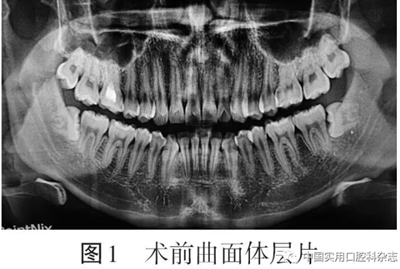

患者男,24歲,以“雙側(cè)下頜智齒拔除術(shù)后2 d伴胸痛”為主訴于2019-12-25來北京大學(xué)口腔醫(yī)院口腔頜面外科就診?;颊咦允? d前拍攝曲面體層片發(fā)現(xiàn)雙側(cè)下頜第三磨牙阻生(圖1)

否認(rèn)反復(fù)牙齦腫痛病史,于外院拔除雙側(cè)下頜第三磨牙,局部麻醉后使用“高速渦輪機(jī)分牙拔除”,手術(shù)時間約50 min,術(shù)中自覺頸部突發(fā)疼痛、肌肉抽搐,術(shù)后即刻出現(xiàn)胸痛,深呼吸時疼痛加重。術(shù)后第1天轉(zhuǎn)動頸部時出現(xiàn)氣泡破裂音,偶有頭暈,否認(rèn)發(fā)熱、惡心、心悸、呼吸困難,于外院靜脈輸液“美洛西林舒巴坦5 g(每日2次)、奧硝唑200 mL(每日1次)”1 d,自覺癥狀稍有減輕,于術(shù)后第2天來我院就診要求進(jìn)一步治療。臨床檢查:雙側(cè)面頰部自眶下至下頜骨下緣、頸部、鎖骨上及胸部輕度腫脹,皮溫不高,皮色不紅,觸診可及捻發(fā)音(圖2)